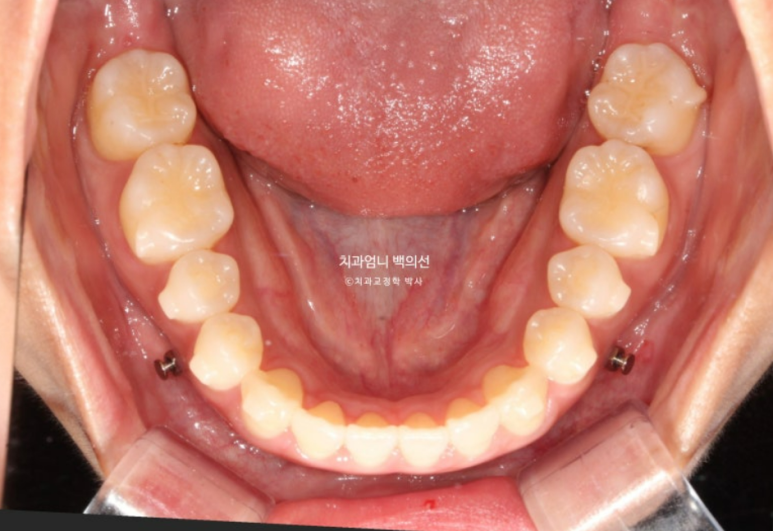

23년 12월 1번장치를 끼기 시작해서 25년 1월까지 총 51개 장치를 다 낀 후 모습입니다.

앞니 개방교합은 해소가 되었지만 앞니 중심선 불일치가 약 1mm 남았습니다.

우측 어금니 교합은 약간 떠있는 상태이고

좌측 어금니 교합은 좋습니다.

배열도 좋습니다.

교정용 나사는 위 2개 아래 2개 총 4개를 식립해서 진행했습니다.

첫번째 세트 51개 장치 안에서 미니스크류를 이용한 상악 어금니 합입과 하악 어금니 후방이동이 잘 일어났습니다.

교합 안정화와 중심선 개선을 목표로 추가장치 제작에 들어갔습니다.

추가장치 갯수는 12개이고 25년 2월부터 4월까지 3달간 꼈습니다.

25년 4월 치료를 마무리 했습니다. 중심선은 이제 정확히 맞습니다.